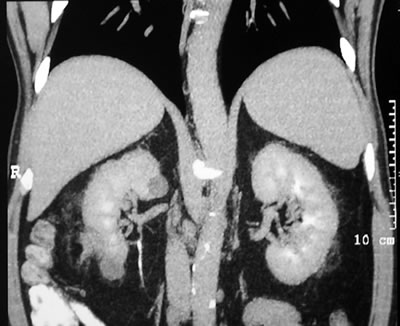

Спиральная

компьютерая томография (СКТ)

в нижнем сегменте правой почки

образование размером 30х33х36 мм, не накапливающее

контрастное вещество (max 15 HU).

|